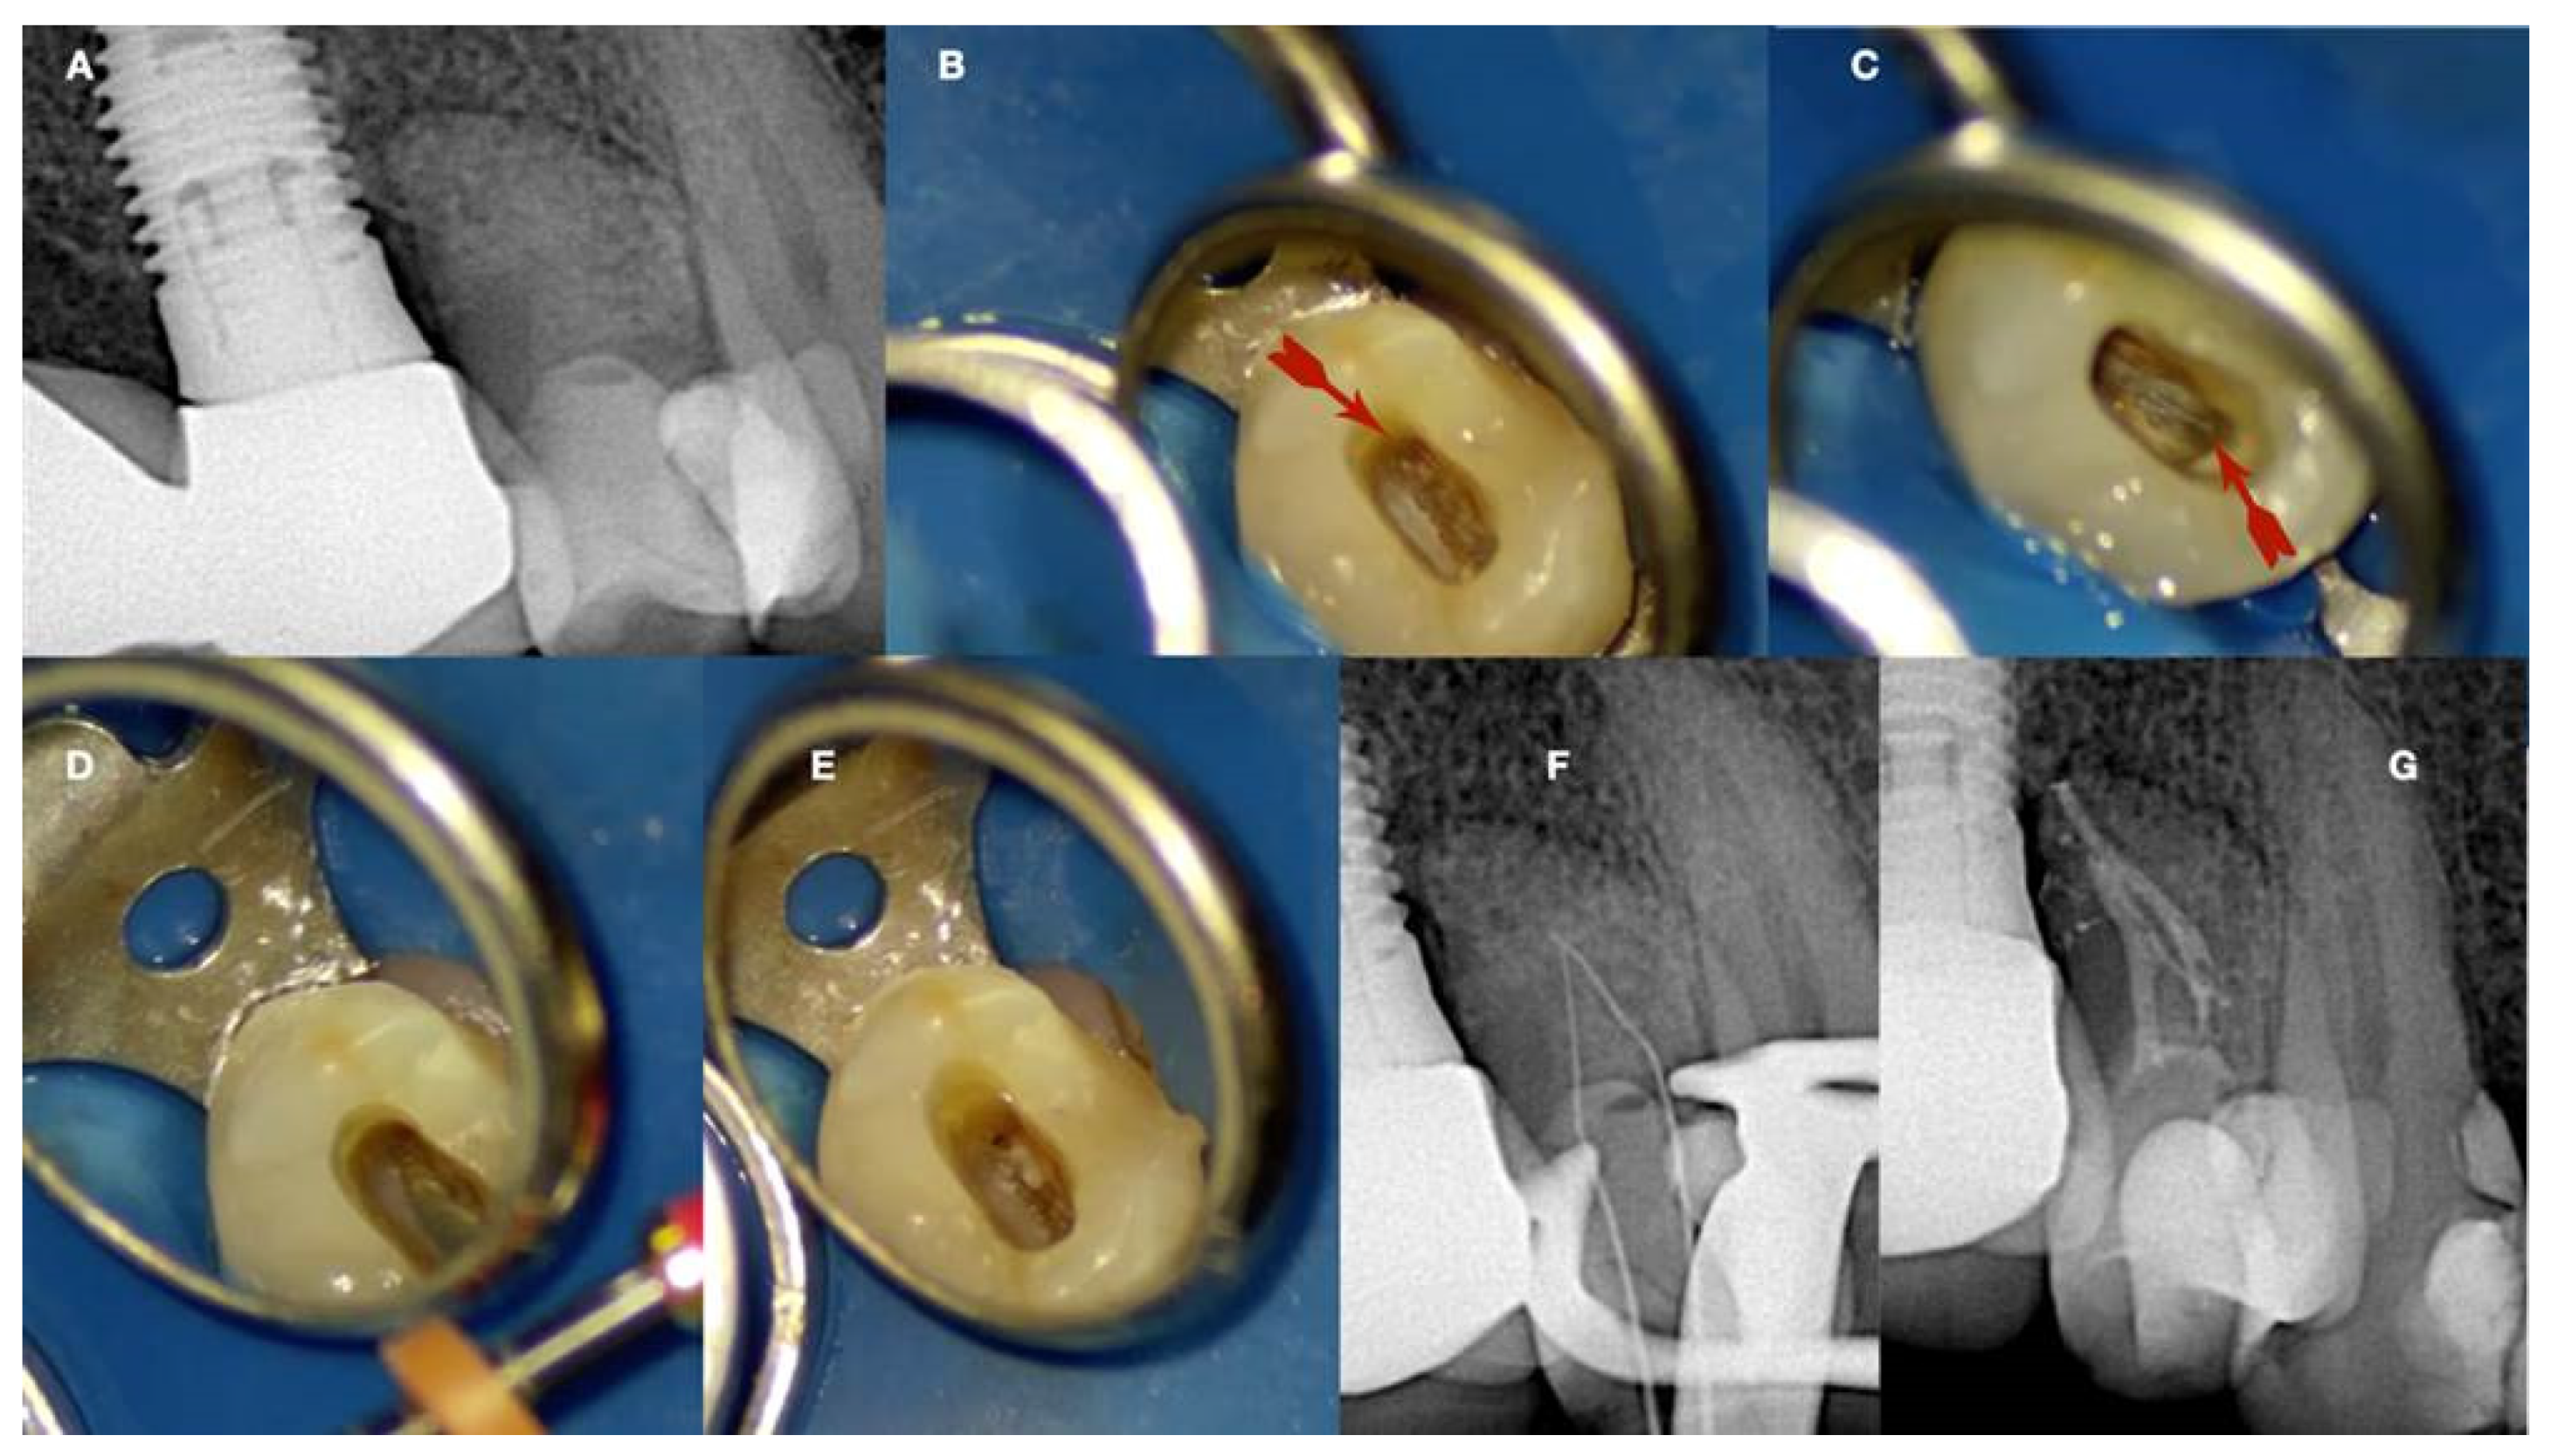

a. Preoperative radiograph of a calcified lateral incisor that suffered a crown fracture. The root canal treatment negotiation was initiated but stopped because of the non-detectable canal and misorientation. The root canal is not visible in the radiograph, b. clinical view of the access cavity after cleaning the debris. The arrow points to a white spot indicating a possible canal, c. higher magnification clinical view. The peripherical dentine is yellow, followed by a central circular grey area that holds a white spot of accumulated debris in the white spot (black arrow), d. A D-finder file (Mani, Japan) negotiating the calcified canal (initial catch). The red circle indicates the arrested misoriented previous access, e. postoperative radiograph, f. Clinical view of the initial glide path file removing pieces of coronal restrictive dentin, g. Clinical view of the calcified canal after the shaping procedures. Transillumination reveals the radial orientation of the dentinal tubules. The reflection of the microscope light gives the characteristic butterfly effect impression (arrows), h. The clinical view of the gutta-percha cut deep inside the canal during post-space preparation.

Figure 6.

Figure 3). Fibrillar calcifications are one of the manifestations of the regressive changes that the pulp undergoes. The incidence of pulp calcifications seems to be relatively high, especially based on microscopic examination because many of the calcifications are not of sufficient size to be discernible in radiographs. Calcifications seem to increase with age, with about 90% of those of 50 yr or older being reported as affected. As teeth age, vascular, lymphatic, and nerve supplies decline, and fibroblasts decrease in size and number (Maeda 2020). A reduction of 15.6% in crown odontoblasts, a reduction of 40.6% in root odontoblasts, and a decreased secretory activity have been observed, suggesting that the reparative capacity of the pulp is compromised with aging. The age-related changes include increases in cross-linkages and the number of collagen fibers, lipid infiltration, and calcifications. Despite many studies having investigated the mechanisms underlying these age-related changes, we still have much to learn about the biological control mechanisms responsible for cellular activity and survival throughout life. The mechanism of hard tissue formation during CM is not yet clear. Several hypotheses have been proposed to explain this phenomenon. Torneck (1990) hypothesized that the deposition of hard tissue is either because of stimulation of the pre-existing odontoblasts or by loss of their regulatory mechanism. On the other hand, Andreasen et al. (1987) described CM as a response to severe injury to the neurovascular supply to the pulp, which after healing leads to accelerated dentin deposition and is closely related to the loss and re-establishment of the pulpal neural supply. Neither mechanism has been proven or studied, and further investigation is required to provide an evidence-based understanding of this occurrence. Calcific metamorphosis is characterized by osteoid-like tissue that is produced by the odontoblasts at the periphery of the pulp space or can be produced by undifferentiated pulpal cells that undergo differentiation because of the traumatic injury (Amir at al. 2001, Pissiotis et al. 2007). This results in a simultaneous deposition of dentin-like tissue along the periphery of the pulp space (root canal walls) and within the pulp space proper (root canal). These tissues can eventually fuse, producing the radiographic appearance of a root canal space that has become rapidly and completely calcified (Paterson & Mitchell 1965). Clinically, there is usually a clear distinction between the calcified irregular tissue and the peripherical dentinal walls reflecting the different histological characteristics and mechanisms of formation of the tissues obliterating the pulp space. Under the magnification and illumination provided by a dental operating microscope, these tissues reflect the light in different ways. Usually, when searching to negotiate a calcified canal under the dental operating microscope the operator evaluates the different dentine colors and textures on the axial view plane. In a single-rooted calcified tooth, the concentric axial orientation of the dentinal tubules is visible under the microscope giving a concentric radial appearance (

Figure 6 and

Figure 7). If not visible, transillumination from a different angle can improve intracanal visibility (

Figure 6).

This concentric radial appearance points to a greyer area in the centre that demarcates the area of secondary and reactionary dentine formation occluding the canal space. This irregular dentine gives a different reflection under the microscope with a more greyish appearance. In the centre of the irregular calcified tissue usually the thin canal space lies. Because of the debris production during deep troughing with burs or ultrasonics, a white spot is created over the canal space dimple demarcating the calcified canal orifice (

Figure 7).